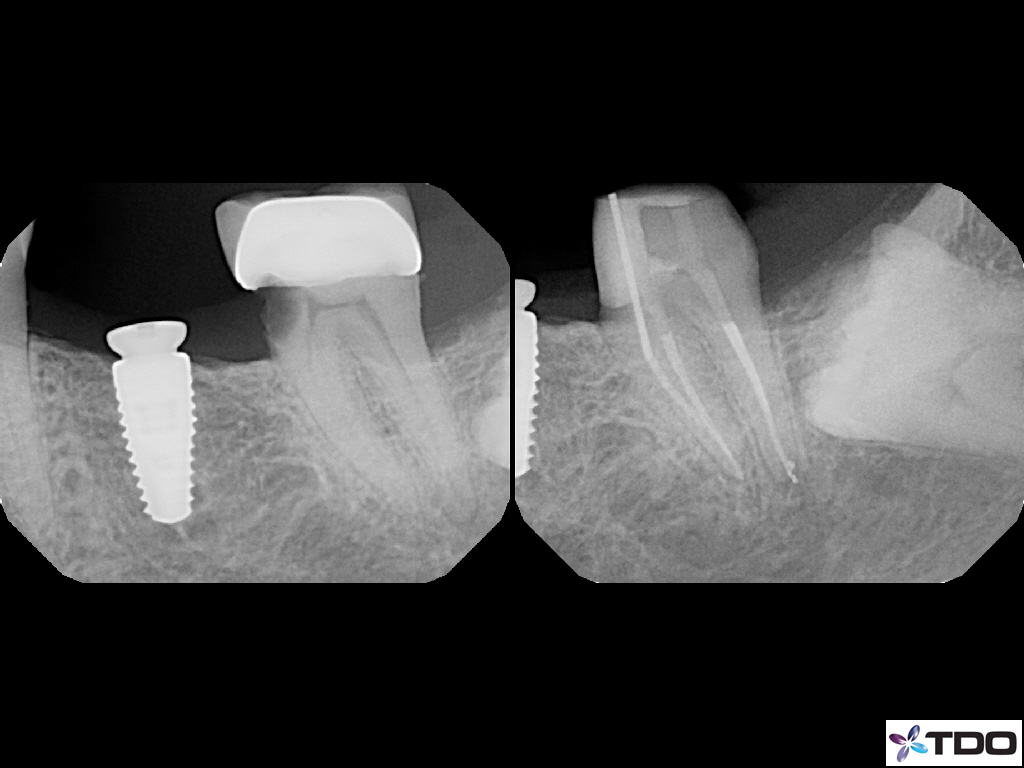

These cases show a level of commitment to conservative endodontics rarely seen in endo today. Plus the restorative excellence is inspiring and should stimulate all endodontists to up their game and help others realize how important the restorative aspect of endodontics is.